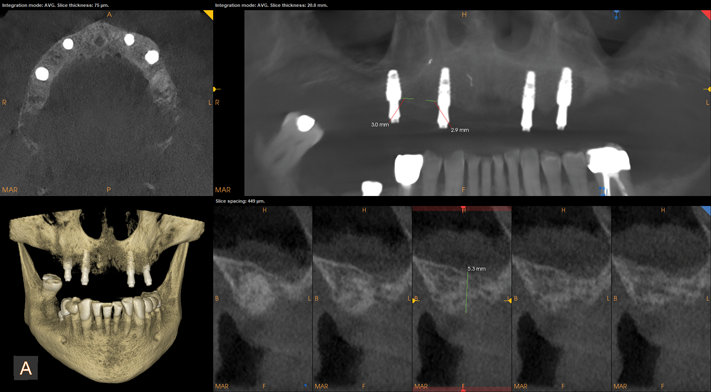

Upon evaluation of the CBCT using a metal artifact reduction (MAR) tool it was determined that either a short implant be placed or an internal sinus elevation procedure be performed to allow placement of a more robust implant. The CBCT showed less than 6 mm of residual bone height (Figure 5) available before the Schneiderian membrane of the maxillary sinus would be breached. After a review of available options, the patient elected to have the sinus elevation done and a longer implant placed with the use of guided surgery. Due to the limited access in the posterior of the oral cavity, the use of a static surgical guide might have proved difficult because of spatial and visual constrictions. Therefore, dynamic virtual navigation was chosen for this procedure.

Fig 5. CBCT revealed residual bone height less than 6 mm.

Figure 5

Fig 8. CBCT at 3-year follow-up

showed new sinus floor and implant surrounded by bone. MAR feature

was used to remove metal scatter.

Fig 10. CBCT revealed relatively non-complex implant placement on

the maxillary right side for the maintenance of 3 mm between each

implant and less than 6 mm residual bone height on the maxillary left

side.